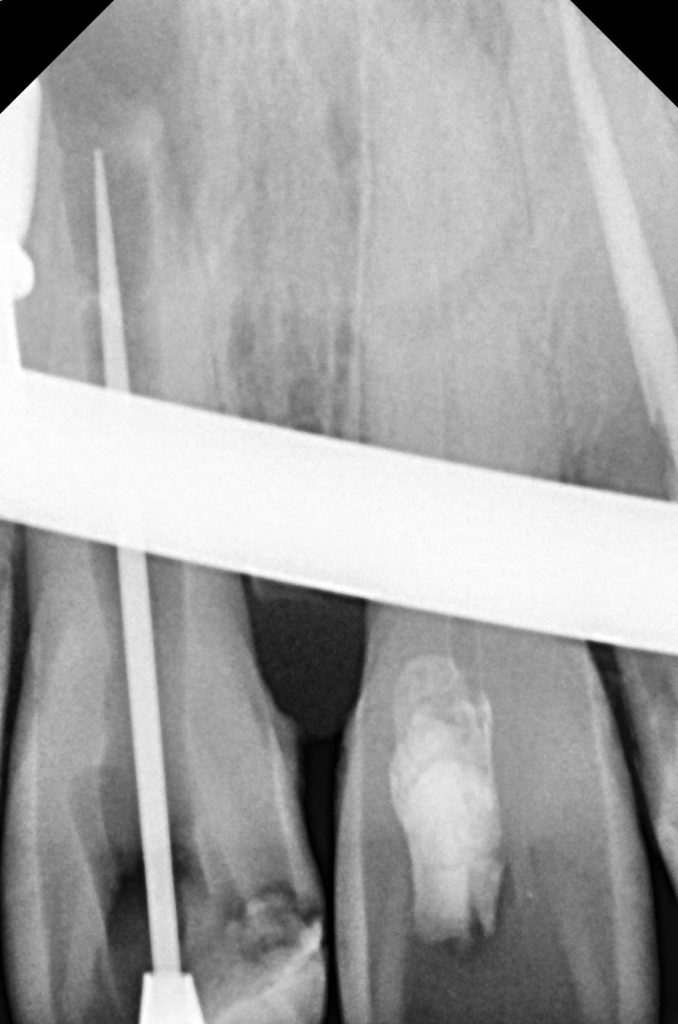

✅ Internal non-vital bleaching for discolored tooth

- Tooth discoloration managed with non-vital bleaching using walking bleach technique.

- Multiple bleaching cycles until desired base shade achieved.

- Allowed stabilization period before shade selection.

Previous MTA apexification provided apical stability, allowing safe buildup and crown retention. Non-vital bleaching minimized aggressive preparation and preserved tooth structure.